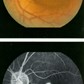

serous macular detachment because of stress

SEROSA CENTRALIS

ANOMALY

This condition is called central serous choroidopathy.

It is characterized by a bullous augmentation in the central part of the retina.

This grows following a leak in the pigment epithelium leaf (= insulating membrane under the retina).

CONSEQUENCE

The patient is more farsighted ("secondary hypermetropisation") and experiencing deformation (=" metamorphosis ") in the central part of the retina.

CAUSE

This disease is known because it occur in relatively young persons (20-50 years, mostly male) with a stressful occupation. Cortisone therapy can also trigger serosa. Some patients have a weak pigment epitelium leaf and can have frequenty a stroke.This is called DRPE: "diffuse pigment epiteliopathy".

TREATMENT

After several weeks, the leak usually disappear spontaneously and reduces the subretinal fluid. Thus, the patient is free of symptoms. So first we consider the injury a few weeks to conservative. In patients where spontaneous recovery is delayed (more than 6 weeks) the doctor can consider a lasercoagulation of the leaking point, when the location isn't too close to the fovea. This limits the duration of the stroke to 1 to 2 months, where normally there's 3 to 4 months duration. 90% of the patients recuperate to 6 / 10 or better.

LATER DEVELOPMENTS

Usually it involves a single disease. After a few months or years the central serous choroidopathie can relapse (estimated at 43%! - In 80% of the cases in the same eye), especially in patients where the pigment epitelium leaf shows elsewhere already defects.